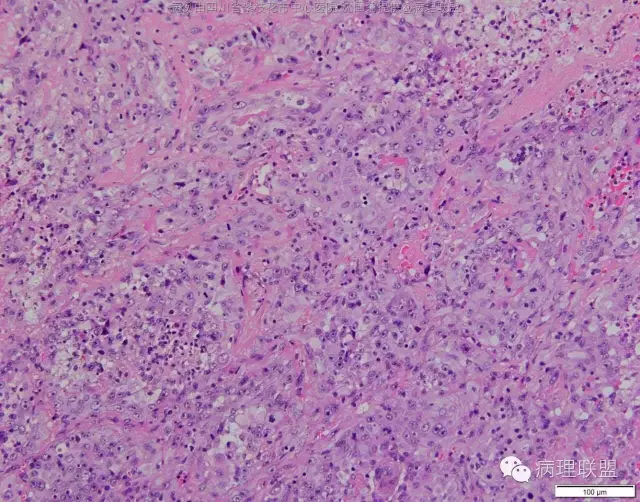

M/47 肺部占位( 肺大细胞癌?)

M/47 肺部占位,大小2*1*0.6cm(病例由四川攀枝花市中心医院 沈国菊提供,致谢!)

@张丽 免疫组化腺癌,鳞癌,神经内分泌,恶黑标记均为阴性,只有广谱CK跟Vimentin阳性,准备发大细胞癌

@沈国菊 肺大细胞癌的签发有时是个排他性诊断,我的体会:大细胞的标准:按淋巴细胞直径3倍来算,需要大于这个值,不能等于(从图给出,符合)。神经内分泌的标记(CD56 SYN CgA)完全阴性的可能性不是没有,建议重做试试;细胞的异型性大(符合);Ki67的指数高,应该非常高(您这里没有给出)。这仅仅是我个人体会,我说的不一定正确。

感谢您的精彩病例,采图非常漂亮,并且有标尺(特别赞)。魏老师,Ki-67阳性大于90%,送检7组淋巴结6/7见肿瘤转移。